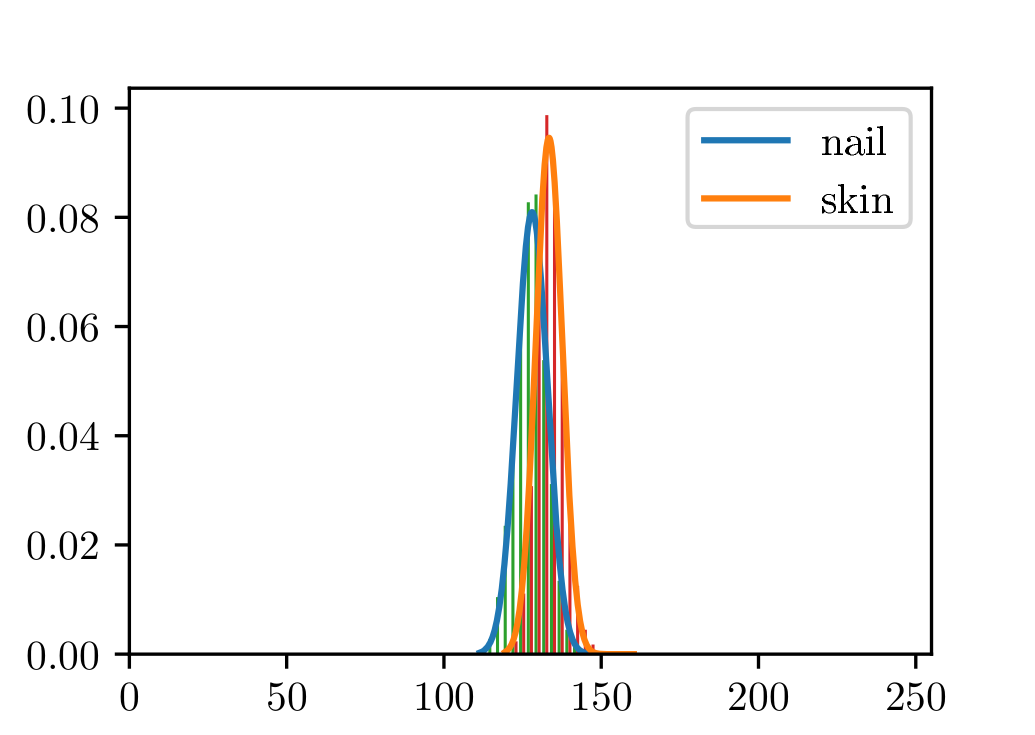

The dataset used in this study was taken in the clinical practice. Following the guidelines of a well-defined medical study, images were acquired in real conditions. All of them were captured in the doctor’s office with their smartphones’ embedded camera. To control some of the environmental conditions, we designed a template to use as the scene background (see Figure 2). During the acquisition process, however, we could not control some other environmental conditions, such as the capture viewpoint the camera setup or the illumination.

Before tackling the image segmentation problem, we perform an image normalization process based on the template’s known measures. It consists on transforming the input image, as seen in Fig. 3 (left), to an image with standard dimensions and orientation, Fig. 3 (right). To achieve our objective we detect the position of the template corners and geometrically transform the image with an affine mapping. As a result, all normalized images appear to had been taken under the same point of view. We remark that the three template colored squares are mapped to the top-right, bottom-right and bottom-left image corners. In particular, left foot images are mirrored. Normalized images are always set to measure pixels. Since the real region inside the template measures cm, a centimetre in the normalized image accounts for 300 pixels, which can be used to measure distances and areas.